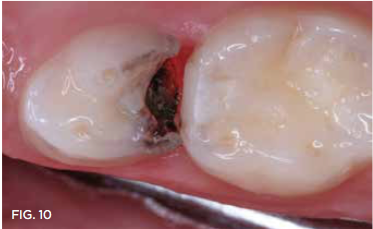

Case 3. This 10-year-old boy was brought to the office for a second opinion regarding restoration of the left primary first molar, which was causing sensitivity (Figure 8). The boy's mother reported that a "tooth-colored filling" had been suggested at another office. The boy was terrified of needle injections and, according to his mother, had required sedation in prior years for restoration of maxillary primary molars. SDF was applied (Figure 9), tooth sensitivity was eliminated, and in 3 months, clinical evaluation and a periapical radiograph confirmed that no other treatment would be needed until the tooth exfoliated (Figure 10 and Figure 11).

Fig 10. 3 months after SDF application, no additional treatment needed.

Fig 10